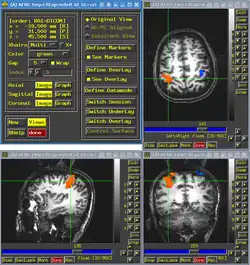

A evolução da imagem do sistema analógico (aquisição baseado em filme) para o formato digital tem sido impulsionado pelas necessidades de redução de custos, com rendimento eficiente e fluxo de trabalho na gestão e visualização de uma proliferação crescente no número de imagens produzidas. Assim como as imagens em formato digital tornam passíveis de metodologias de processamento de imagem para o realce, análise de exibição, o armazenamento e interpretação mesmo aumentada. Por causa da onipresença de imagens em biomedicina, a disponibilidade crescente de imagens em formato digital, a ascensão do hardware de alta potência computador e redes e, a comunhão de soluções de processamento de imagem, imagens digitais tornaram-se um tipo de dados central que deve ser considerada em muitas aplicações informática biomédica.[2] A criação de um padrão internacional para imagens médicas e informações relacionadas, o DICOM (Digital Imaging and Communications in Medicine) que define os formatos das imagens médicas padronizaram a forma de armazenamento de informações de uso clínico. [3]

Imagens digitais

Uma imagem digital é tipicamente representada num computador por uma matriz bidimensional de números (um mapa de bits). Cada elemento da matriz representa a intensidade de uma pequena área quadrada da imagem, chamado um pixel. Se considerarmos a imagem de um volume, então é necessária uma matriz tridimensional de números; cada elemento da matriz representa neste caso um elemento de volume, chamado um voxel.

Podemos armazenar qualquer imagem num computador desta maneira, quer convertendo-a de um análogo de uma representação digital ou gerá-la diretamente sob a forma digital. Uma vez que uma imagem é em formato digital, que pode ser tratada assim como todos os outros dados. Ele pode ser transmitido através de redes de comunicações, armazenadas de forma compacta em bancos de dados em meios magnéticos ou ópticos, e exibidos em monitores gráficos. Além disso, a utilização de computadores tem criado um campo completamente novo de capacidades de geração e de análise de imagem; imagens podem ser calculadas em vez de medidas diretamente. Além disso, as imagens digitais podem ser manipuladas para exibição ou análise de formas que não são possíveis com imagens baseadas em filmes.

Em geral, existem duas estratégias diferentes em imagem do corpo: delinear a estrutura anatômica (imagens anatômicas / estrutural), e determinar a composição ou a função (imagem funcional) do tecido. Na realidade, não se escolhe entre imagens anatômicas e funcionais; muitas modalidades fornecer informações sobre ambos, morfologia e função. No entanto, em geral, cada modalidade de imagem é caracterizada principalmente como sendo capaz de processar imagens de alta resolução com boa resolução de contraste (imagens anatômicas) ou para renderizar imagens que retratam a função do tecido (imagiologia funcional).[2]

Os vários métodos de imagiologia diferem de radiologia de acordo com dois eixos mais informações de imagens, a resolução espacial (detalhes anatômicos) e informação funcional descrito (que representa o tecido composição- por exemplo, normal ou anormal). Uma amostra das modalidades de imagem mais comuns é mostrado.[2]